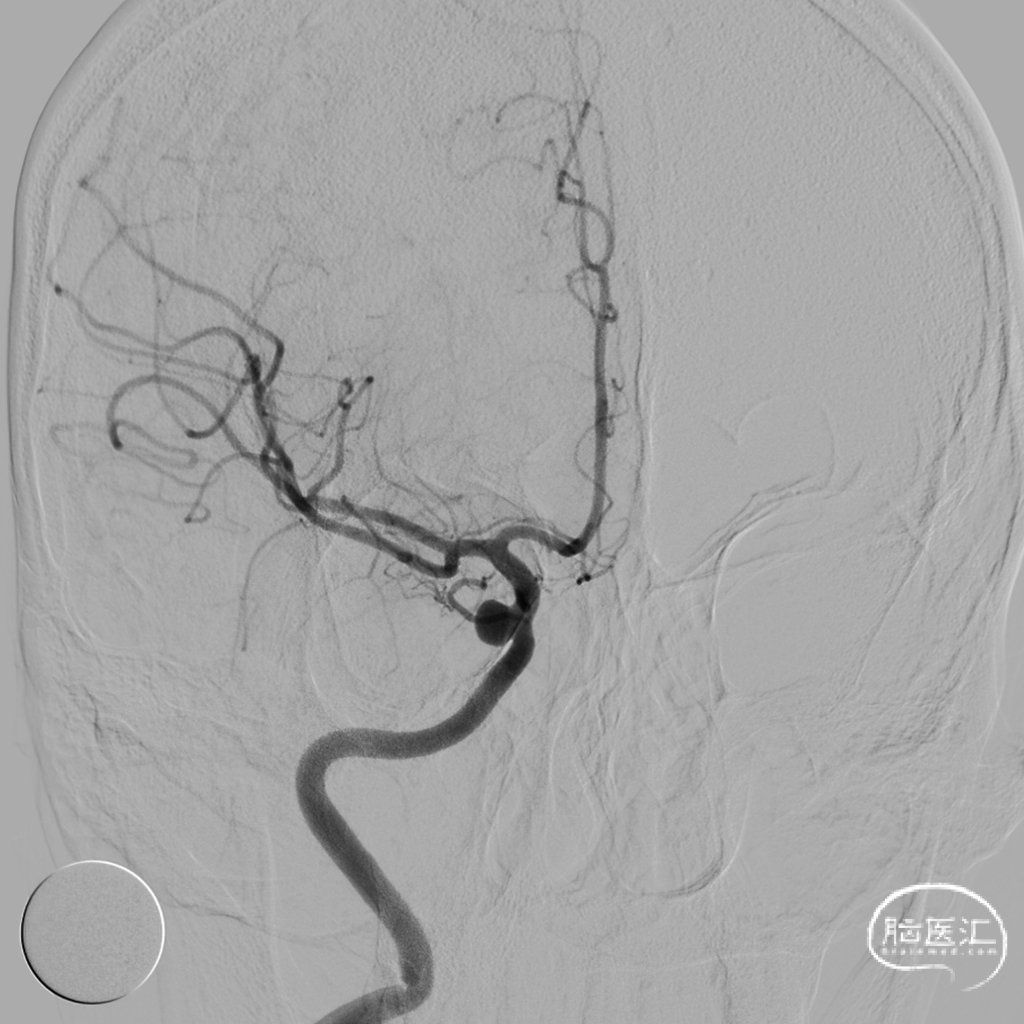

2021-12-20 脑血管造影:

左侧颈内动脉多发动脉瘤;右侧颈内动脉床突段动脉瘤。

LICA 多发动脉瘤,大小分别为3.09×3.79mm、1.73×1.73m及1.79mm×1.63mm,载瘤动脉远端直径为3.11mm,近端直径3.49mm。

RICA 床突旁动脉瘤 6.56×5.29mm ,载瘤动脉近段直径约3.66mm,远端直径3.40mm。

2022-2-21 右侧颈内动脉血流导向装置重建术(Tubridge)

R-ICA血流导向装置(Tubridge3.5*20mm)